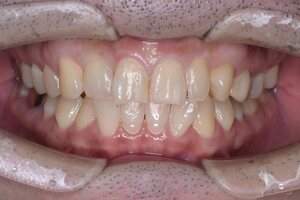

症例③ CR

治療前

治療後

年齢 40代・女性

主訴 前歯の黒いのが気になる

治療内容 右上2番、左上2番

治療費 約2.200円(保険診療3割負担)

(2022年6月現在)

治療期間 1日

リスク・副作用 麻酔がきれた後に痛みがでる可能性がある。

治療方針 両側共に頬側遠心から隣接にかけて、虫歯をとって、CRをつめる。

特記事項 虫歯になりやすい方なので、歯間の清掃指導を行った。

担当者所見 虫歯が歯髄近くまで広がっており、しみるのが続く場合は抜髄の可能性がある。